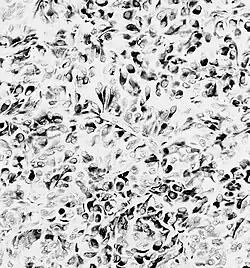

Gwiaździak zarodkowy (łac. astroblastoma, ang. astroblastoma) – pierwotny guz ośrodkowego układu nerwowego, o niewyjaśnionej histogenezie i nieokreślonym stopniu złośliwości według WHO.